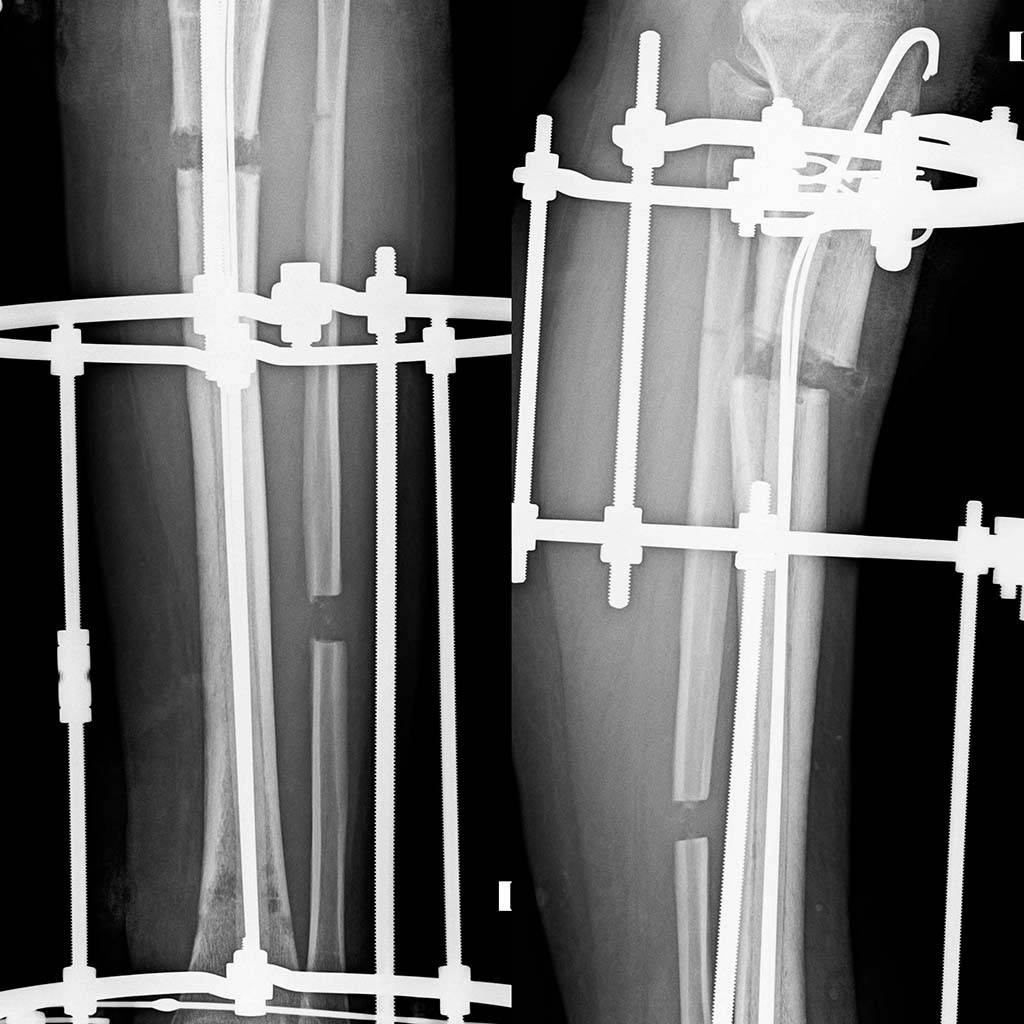

Спасибо всем, кто принял участие в обсуждении. Штифт удален, спейсер

ванкомицин 2г + амикацин 1,5 г. Через 2-3 недели планируется удалить

спейсер и наложить спице-стержневой аппарат Илизарова. Рентгенограммы

прилагаются.